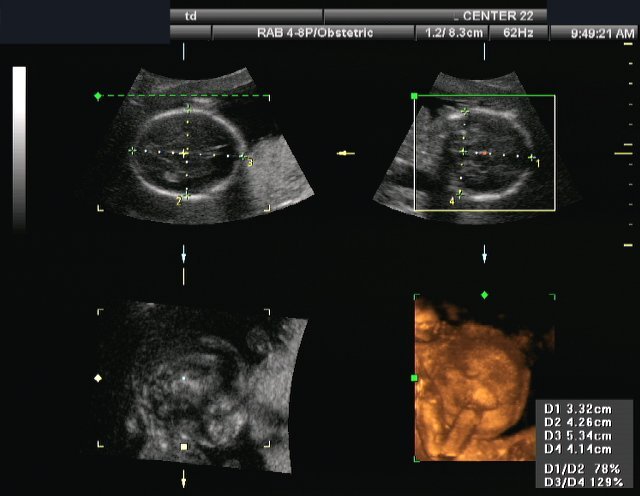

The modern ultrasound machines are able to show two-different images simultaneously. They can visualize the grayscale ultrasound picture of the body tissues together with a color visualization of the blood flow, based at the Doppler Effect. The color is layered over the greyscale ultrasound image, allowing the ultrasound operator to obtain information for the blood flow in arteries and veins and at the same time observe the surrounding tissues.

Duplex: Duplex ultrasonography provides a color picture detecting the blood flow and a two-dimensional greyscale ultrasound image of the tissues.

Duplex: Duplex ultrasonography provides information about the presence of blood flow in the studied vessels, as well as its direction, speed, turbulence, etc. together with an image of the surrounding tissues.